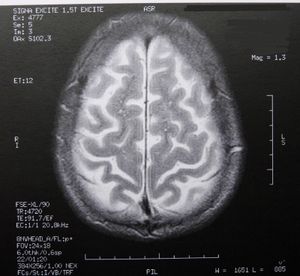

Gehirn: Rätsel der Faltung gelöst. Bild: pixelio.de, Dieter Schütz